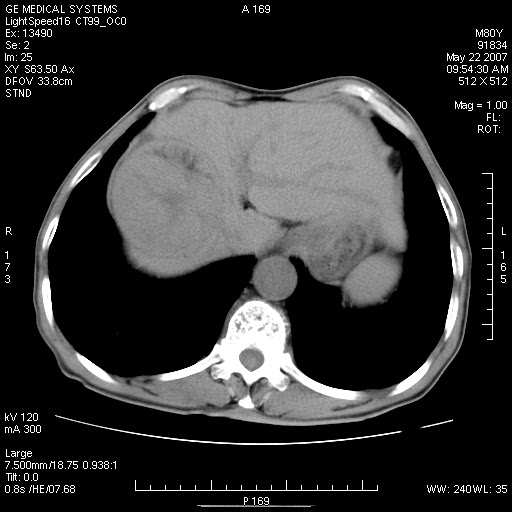

标题: CT8346:男,80岁。血尿,肝脏,膀胱占位,是否为肝转移?

男,80岁。血尿,无腹部不适病史。

肝脏病变:

看看平扫的,再看看增强动脉期的,怎么也不是囊肿。

肝脏内病灶有假包膜,增强扫描动脉期有动静脉瘘,有快进快出特点,考虑原发性肝癌。病灶内有裂隙样低密度影,以纤维板层样细胞癌可能性大。膀胱左侧乳头状占位,增强呈明显强化,左侧盆腔内有肿大淋巴结,结合有血尿病史,考虑膀胱癌左侧盆腔淋巴结转移。